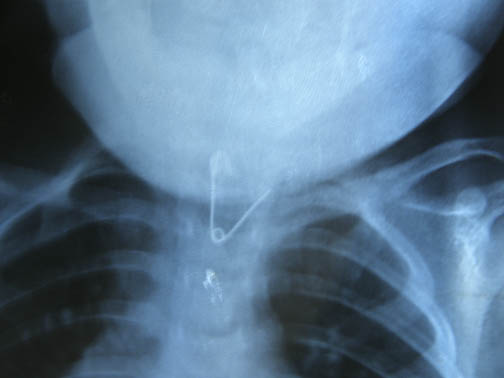

Un sabato da odissea quello vissuto da una famiglia di Fornaci di Barga coinvolta in un caso di “sanità superficiale” o inadeguata. Protagonista di questa avventura, per fortuna finita senza conseguenze, una bimba di 10 mesi, Amelia; ed è stato solo grazie a tutta la volontà dei genitori che il pericoloso oggetto estraneo è stato rimosso.Amelia sabato pomeriggio aveva ingerito una spilla da balia mentre si trovava nel suo lettino. La spilla era attaccata ad un’immagine di Sant’Antonio appesa sul letto. L’immagine deve essere caduta e la bimba ha staccato la spilla e poi l’ha ingerita.“Erano le 16,30. Con mia madre abbiamo immediatamente portato la bimba all’ospedale di Barga – ci dice la mamma G.L., 36 anni – e dopo aver atteso il medico del primo soccorso per venti minuti la risposta del sanitario è stata che era impossibile che fosse successa una cosa del genere perché la bimba stava bene”.In un primo tempo il medico si è rifiutato di fare una radiografia per individuare la spilla e solo dopo le insistenze della madre ha telefonato a

ll’ospedale di Castelnuovo, dato che a Barga era al momento impossibile utilizzare la radiologia, per assicurarsi che fosse possibile fare una lastra.

Madre e nonna sono corsi così a Castelnuovo dove la radiografia ha confermato la presenza nella gola della spilla da balia; aperta e quindi particolarmente pericolosa soprattutto se dalla gola fosse scesa nello stomaco.

A Castelnuovo ci hanno detto che loro potevano solo tenere la bimba sotto controllo, ma che non erano in grado di asportare la spilla – ci dice ancora la mamma – Nessuno sapeva cosa fare e così, esclusivamente di nostra iniziativa, io e mio marito abbiamo deciso di portare Amelia al Meyer di Firenze ed abbiamo chiesto che fosse fatta intervenire un’ambulanza.

Altri venti minuti di attesa e poi l’ambulanza è arrivata. “Grazie alla generosa disponibilità del comandante della compagnia Carabinieri di Castelnuovo, cap. Donato Manca (il padre della bimba è appuntato proprio a Castelnuovo), il mezzo è stato scortato fino a Firenze da una pattuglia del NOR e così Amelia è arrivata all’ospedale alle 20,15. “Qui il trattamento che ci hanno riservato è stato davvero di tutt’altro genere – dice la mamma . La bimba è stata subito operata e dopo un’ora era tutto finito. La spilla era stata rimossa senza che avesse causato nessuna conseguenza”.

Amelia,mia figlia